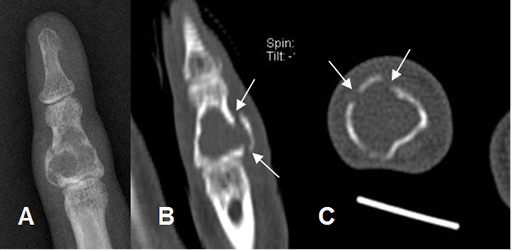

Fig 88. Encondroma.

A: Rx AP, B: TAC reconstrucción coronal y C: TAC axial. Lesión expansiva y lítica en la falange proximal del 5º dedo, con ruptura de la cortical, (Flechas) que corresponde a encondroma.